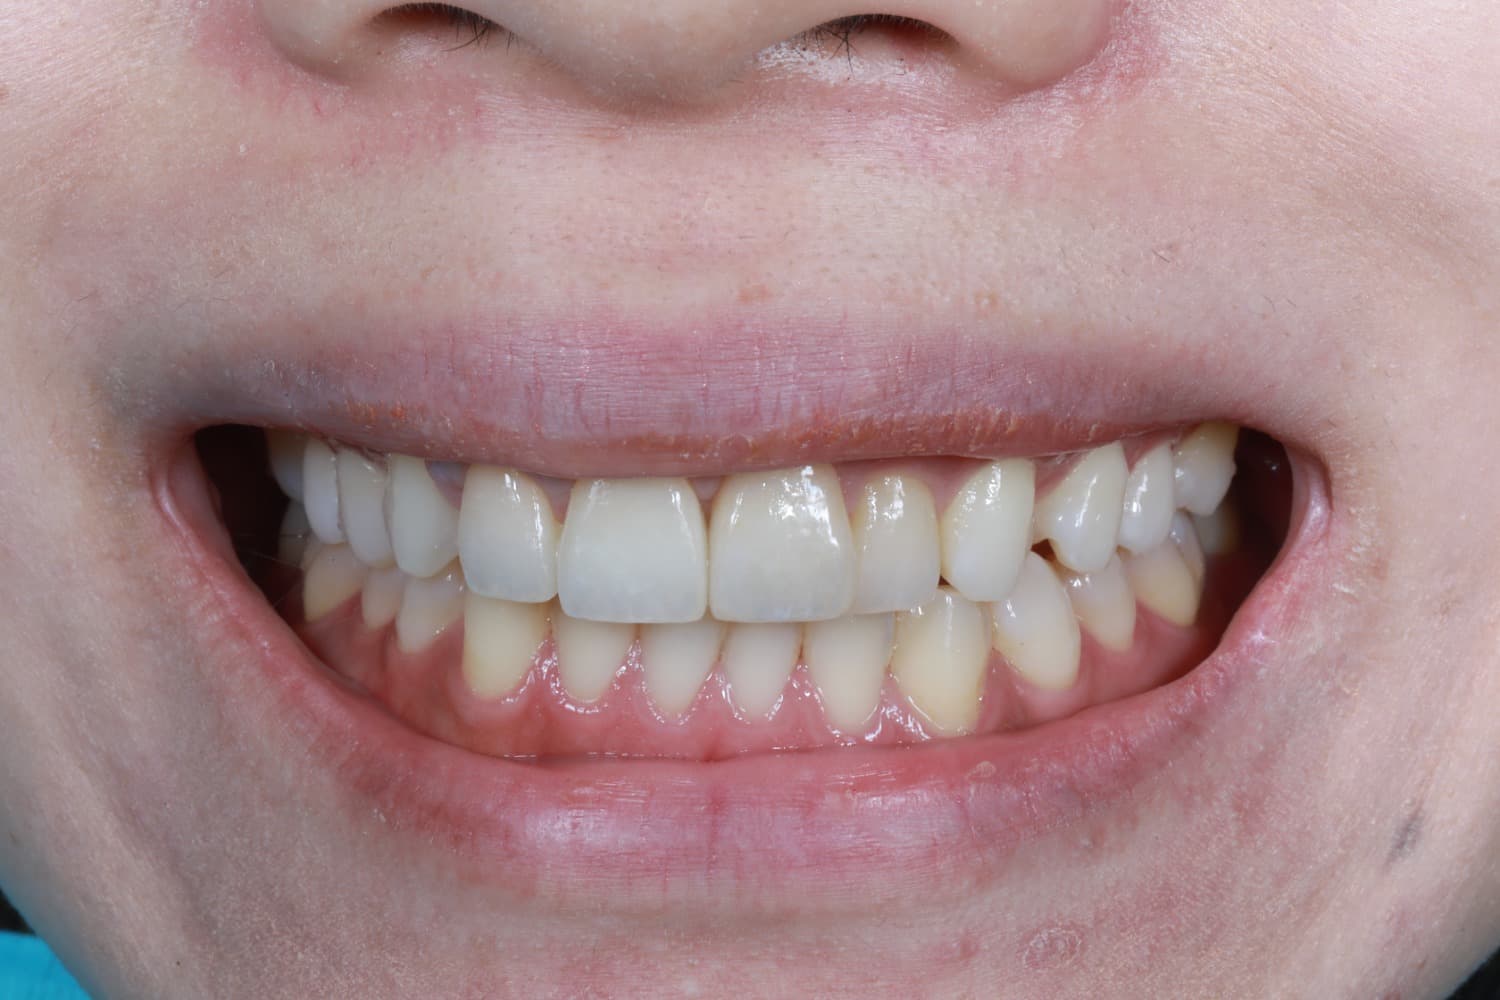

Before

After

喪失した連続欠損に対してインプラントGBRCTGを行い、審美的・機能的に回復を行なった

年齢

30代

性別

男性

主訴

前歯の入れ歯を避けたいのでインプラントをしてほしい

治療期間

2年

治療回数

20回

費用

200万円

副作用・リスク

腫脹、疼痛